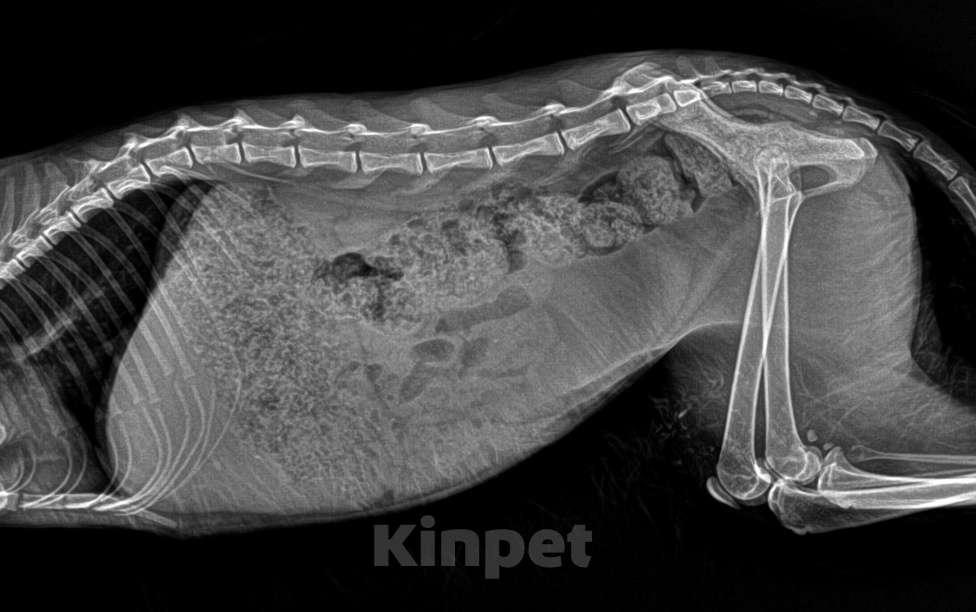

‼️Ирис ИЩЕТ ДОМ‼️МОСКВА И МО📣 Нашли уличного котёнка,возраст примерно 8-10 месяцев Срочно ищем добрые руки и хороших хозяев, кто сможет пристроить себе в дом❤️‍🩹 Трёхцветная, красивая кошечка (кончики ушей чуть чуть вислоухие), сейчас еще пугливая, ей нужен свой человек, который вернет ее доверие, видно, была домашняя Оставить у себя не можем.. Ходили к ветеринару, проблем особых нет Скорее всего не стерилизованная, но не проверяли, нужно вести на узи ✔️Девочка ✔️Трёхцветная ✔️Ест сухой корм ✔️Не агрессивная ✔️Есть вет паспорт ✔️Обработана от паразитов ✔️Приучена к лотку В подарок отдам пуходёрку, 2 керамические миски, манеж, корм Город Москва, находится дома в районе Северное Тушино